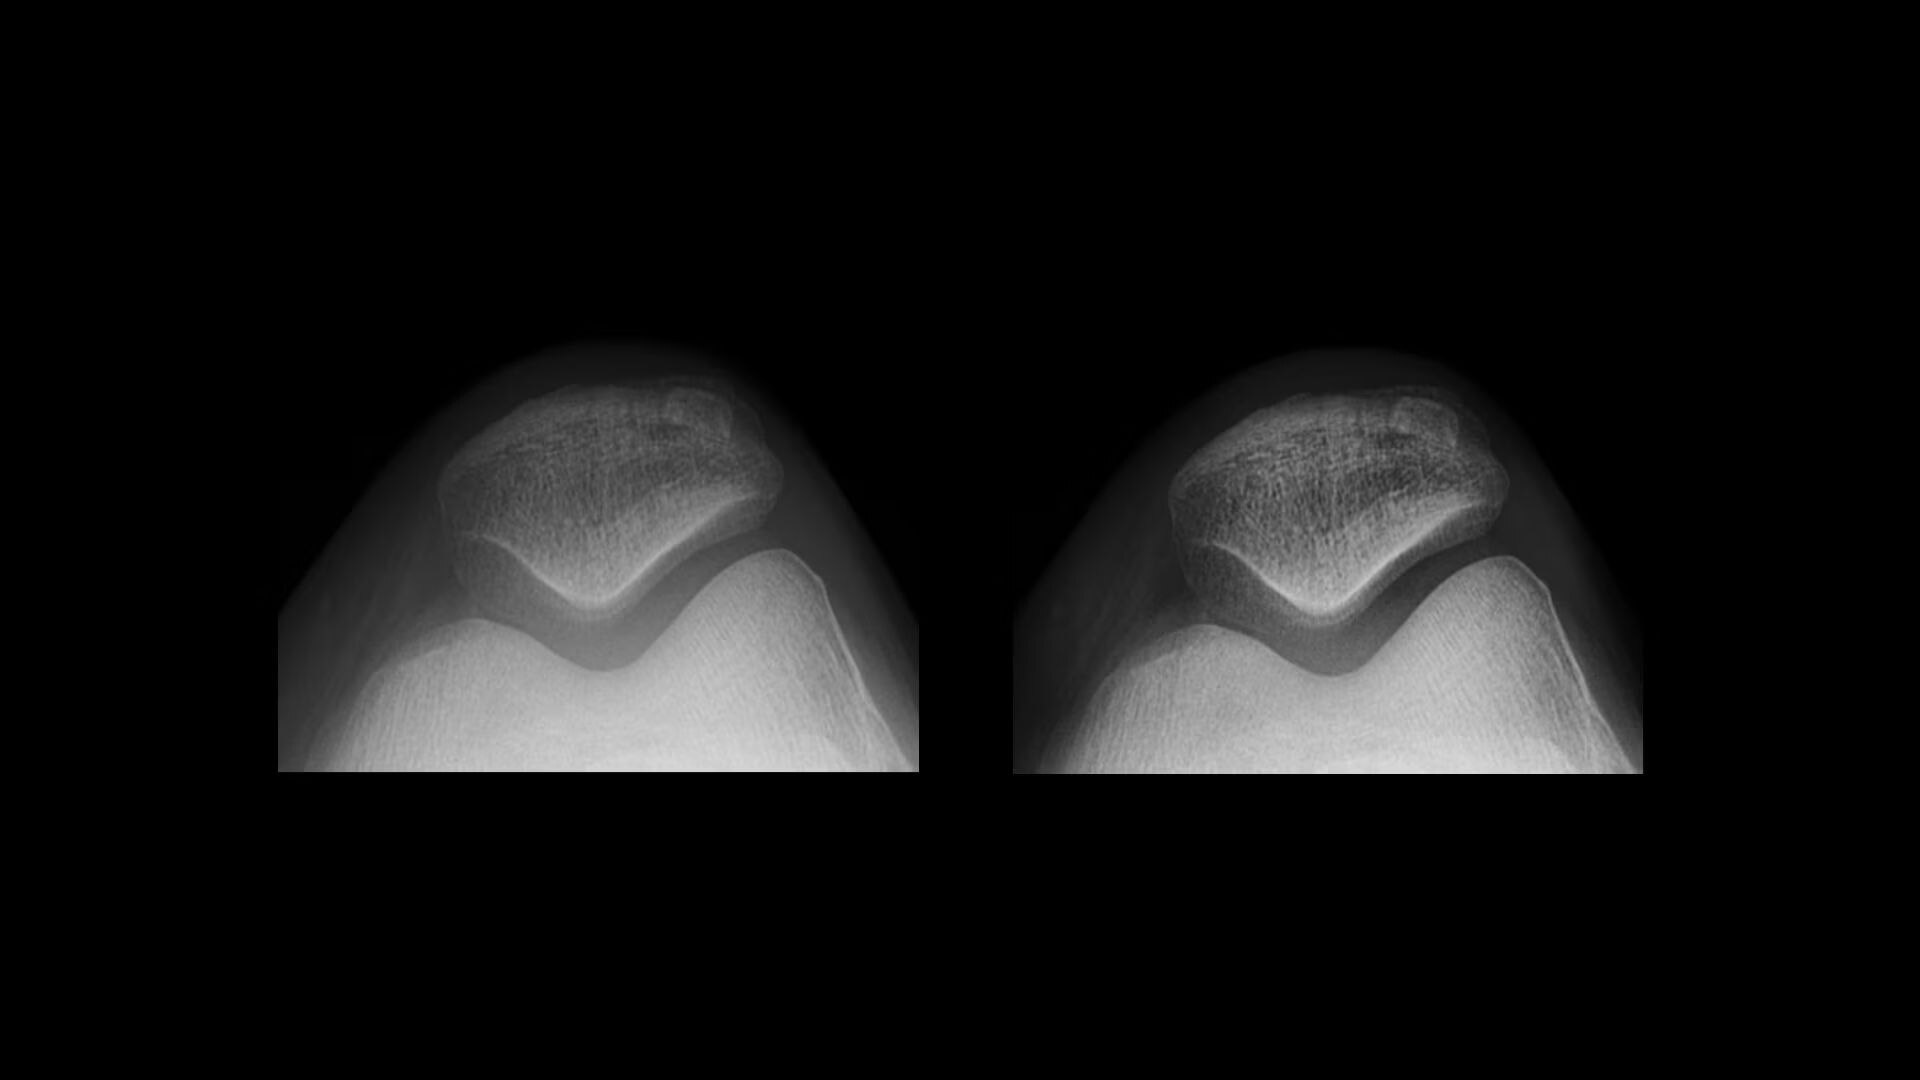

Reduced noise

Reduce noise levels

Detail Preserving Noise Reduction Filter (DPNR) offers significant noise reduction capabilities while minimizing the effect on fine details. DPNR provides adaptive noise reduction based on the image with an edge-preserving filter to maintain edge details. It has three levels of reduction (low, medium and high).